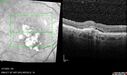

Pseudophakic cystoid macular edema (CME)158 views66 year old female 4 months following cataract surgery. Never had very good vision after surgery. On PF QID for one month. VA 20/50 in both eyes.